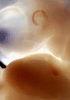

Most embryos at stage 16 are approximately 37 postovulatory days old and measure 11-14 mm in length. Distinguishing criteria for this stage include the external appearance of retinal pigment, the nasal pits face ventrally, pharyngeal arch 2 is more massive and conspicuous than arch 3, auricular bumps begin to appear, and the thigh, leg, and foot can be distinguished in the lower limb.

Photographs